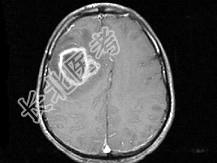

- 单项选择题男,49岁, 头痛、左侧肢体不能活动1周,PE: 左上下肢肌力O级,根据所提供图像, 最可能的诊断是 ( )

A、(右额顶)脑结核

B、(右额顶)脑转移瘤

C、(右额顶)脑脓肿

D、(右额顶)脑膜瘤

E、(右额顶)胶质瘤